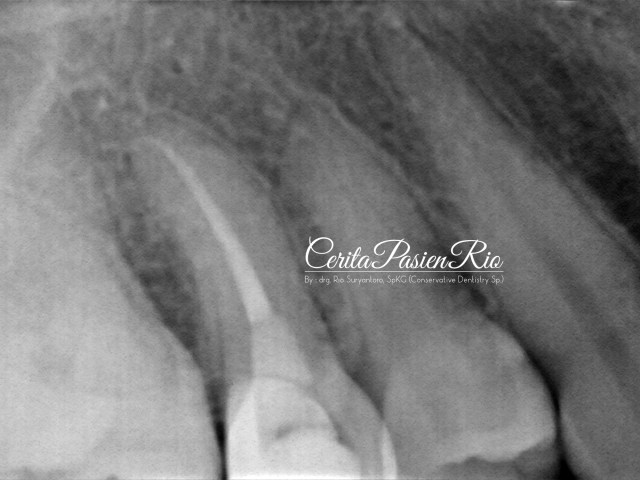

kemudian, saya lakukan foto rontgent dengan keadaan seperti dibawah ini.

gambar 3. foto rontgent dental menunjukkan adanya kehilangan jaringan gigi yang cukup banyak dimulai dari bagian proksimal distal.